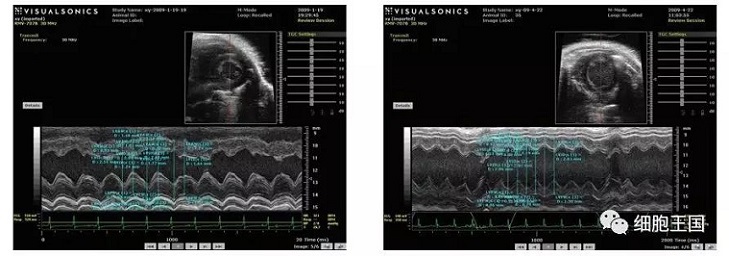

2010年暨南大學(xué)醫(yī)學(xué)院血液病研究所李軍研究小組,在間充質(zhì)干細(xì)胞抗衰老作用的動(dòng)物實(shí)驗(yàn)中發(fā)現(xiàn),干細(xì)胞移植組存活日期明顯長(zhǎng)于對(duì)照組,移植3個(gè)月后評(píng)價(jià)心功能的指標(biāo),心脾質(zhì)量指數(shù),器官組織學(xué)衰老程度評(píng)分結(jié)果以及血生化指標(biāo)皆優(yōu)于對(duì)照組,證實(shí)移植干細(xì)胞能有效地延緩衰老進(jìn)程。

干細(xì)胞移植后各臟器呈現(xiàn)較之前狀態(tài),具體表現(xiàn)在以下幾個(gè)方面(如圖)。

超聲心動(dòng)圖顯示對(duì)照組左室舒張期容積低于移植組